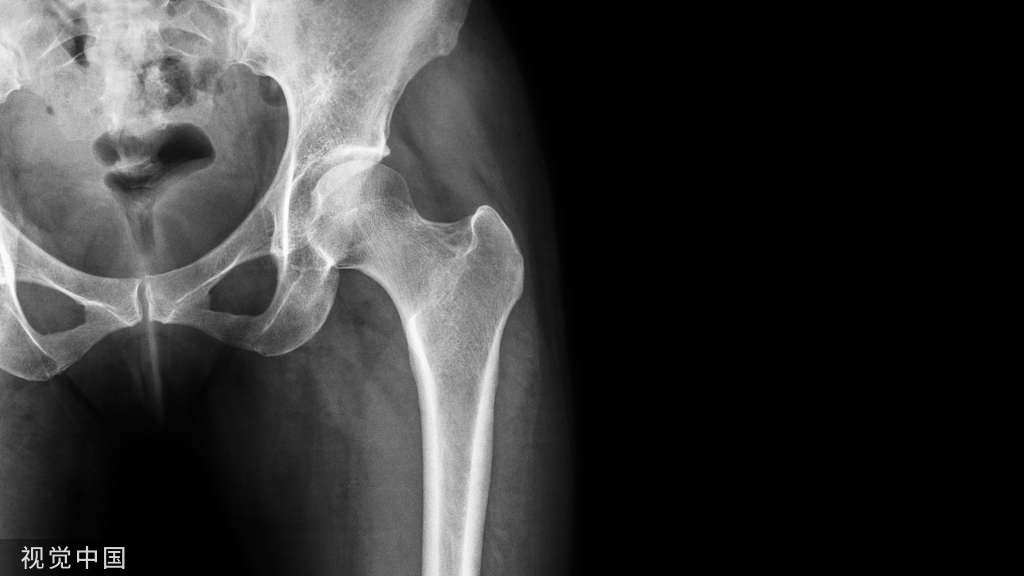

腓肠肌分为内、外两个肌腹,内侧头起自股骨内侧髁上的三角形隆起,外侧头起自股骨外侧髁的近侧端。两个头的肌束向下,在小腿中部结合形成跟腱,止于跟骨。

辅检:MRI、X线片、超声等。

B超或核磁共振(MRI)检查,可以明确损伤位置。